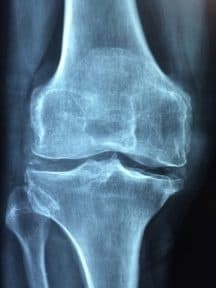

Osteoporosis is a condition where the bones can weaken and become brittle and prone to fractures from even the mildest stresses such as bending or coughing. Older women, especially Caucasian and Asian women, are at a much higher risk of developing osteoporosis. As this condition weakens the bones, fractures related to osteoporosis are common and often occur in the spine, wrist and hip.

Your bones are a dynamic system and are being constantly renewed – old bone is broken down and new bone is made. Osteoporosis occurs when new bone creation is unable to keep up with the loss of previous, old bone. Younger people’s bodies break down and build up new bones much faster, but this process can slow down as people age.

Doctors often test for osteoporosis by first reviewing medical history and then conducting a physical exam. There may also be a blood and urine test to look for conditions that can cause bone loss. There may also be a bone density test conducted to determine whether or not you’re at risk for osteoporosis. If you do have osteoporosis, the doctor will likely create a treatment plan that includes medications and lifestyle changes. There currently is no cure for osteoporosis, however, proper treatment can strengthen and protect bones.